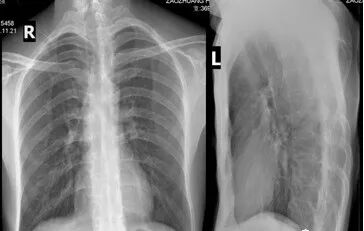

(二)病理 神经受压损伤常为假炎性肿胀样,感觉纤维最先受累,运动神经仅在晚期出现受压。此症状严重,较难恢复。神经受压时间过久则会通过交感神经导致血管舒缩障碍。锁骨下动脉血管壁可发生改变,动脉外膜增厚,间质水肿及同膜增厚伴管腔内血栓形成。早期血栓为纤维素血小板型,可出现雷诺(Raynaud)现象。 交感神经纤维收缩反射可加重指尖血管阻塞。 静脉在过度外展或内收时受到压迫,可观察到血液逆流停滞和外周静脉压上升,压迫消失后恢复正常。静脉壁反复损伤可发展类似炎症后纤维化样改变,静脉呈白色,失去半透明状态,且口径明显减小,形成侧支循环。早期发展趋势为静脉血栓,如侧支循环尚未形成,则可引起指端坏死改变。 临床表现 临床表现常见于中年妇女,20~40岁占80%,多有颈部外伤史。临床症状差异很大,且不持续 。分为神经受压和血管受压两类,神经受压的症状较为多见,也有神经和血管同时受压。 神经受压症状:有疼痛,感觉异常与麻木,常位于手指和手的尺神经分布区,也可在上肢、肩胛带和同侧肩背部疼痛并向上肢放射。晚期有感觉消失,运动无力,鱼际肌和骨间肌萎缩,4~5指伸肌麻痹形成爪形手。 臂丛神经受压:臂丛神经以跨越第1肋骨的下干最易受压,上干受压的较少,主要表现是臂丛神经下干受压的症状。 病人主要表现为:患侧肩部及上肢疼痛,无力,发病早期疼痛为间歇性,可向前臂及手部尺侧放射,肩外展及内旋时疼痛加剧。严重者可出现前臂及手部尺侧的感觉异常,甚至出现肌肉瘫痪,肌肉瘫痪及萎缩以小鱼际及骨问肌为甚,表现为爪形手畸形,有时也存在大鱼际肌及前臂肌肉肌力减退,锁骨上区有压痛并向前臂放射。 血管受压:一般病人不出现严重的血运障碍,当病变刺激血管时,可出现上肢套状感觉异常,患肢上举时感发冷,颜色苍白,桡动脉搏动减弱,锁骨下静脉严重受压时,则出现患肢远端水肿,发绀。血管严重受压时可出现锁骨下血管血栓形成,肢体远端血运障碍。 病史及症状: 既往史:大多数患者均有较长健康搜索的颈肩痛病史。 主要症状:本病的主要表现为颈肩部酸痛和不适,可向肩肘部放射患肢无力健康搜索,患者睡觉时患肢怎么放也不舒服可伴有头晕、耳鸣等症。 首诊时间:约30%的病例是在发病1年之内来诊,半数患者在1~2年来诊,另有20%患者超过2年来诊。 发病肢体:以非优势手多发,占2/3以上。 发病特点:急性发病者占55%慢性发病约占45%。 疼痛性质:均与体位关系密切,95%的患者呈间断性发作。 其他症状:几乎全部病例均有颈肩背部的异常、不适感约半数伴有疼痛。此外几乎95%的病例在睡觉时感到患肢怎么放也不舒服,同时伴有肩上举无力,少数患者可出现耳鸣、头昏及屈肘无力感。 诊断及鉴别诊断 1.诊断: 根据病史、局部体检、胸部和颈椎X线摄片和尺神经传导速度测定,一般可以明确诊断。 由于TOS患者临床表现复杂,与多种神经卡压症(如肘管)及运动神经元性疾病等症状相似,因此一种检查方法无法满足需要。 皮肤痛阈试验和两点辨别试验用于对中、晚期病人的诊断。而症状激发试验是最主要的早期诊断方法,包括“艾德森氏”试验、“过度外展”试验、“锁骨上叩击”试验、“上臂缺血”试验等。 1)“艾德森氏”征 病人端坐,双手置于膝上,将头转向患侧,下颌抬起使颈伸直,嘱病人深吸气后屏气,如桡动脉搏动减弱或消失者为阳性 2)“过度外展”试验 病人取坐位,检查者一手触摸病人桡动脉,同时将上臂被动地过度外展,如桡动脉搏动减弱或消失,腋下出现杂音者为阳性。 3)上臂缺血试验(一般认为最可靠) 即患者双上臂抬起,前臂屈曲90°,肩外展外旋,交替握拳与松开,若3min内一侧产生疼痛或不适而被迫下垂为阳性。 2.影像学 胸廓出口综合征主要依赖临床特征诊断,影像学有助于了解受压部位,解剖特征,确定手术方案:影像学检查X线颈椎片和胸片可以排除颈肋、第7颈椎横突过长、锁骨、第一肋骨畸形或其它骨性病。 平片——骨质异常 平片可以排除骨性结构的异常,图中两人都是临床证实的胸廓出口综合征的病人。 左图可以发现病人存在第七颈肋及颈七椎体横突过长; 右图则是锁骨骨折后骨痂过度形成而导致的肋骨锁骨间隙狭窄。 多普勒超声可以发现血管受压狭窄,血管造影可以确定狭窄和受压的部位: 评价动脉受压病变 静脉受压评估欠准确 臂丛显示不清 CT血管造影可用于评价动脉受压病变,图来自一个37岁的男性,图a是正常状态下的矢状位,锁骨下动脉没看到明显受压,图b是该病人手臂外展时的矢状位图,可以看到锁骨下动脉受压变窄,图cVR图直观显示血管跟周围骨骼结构的关系。值得注意的是,影像学对于静脉受压的评估相对欠准确,因为即使在正常人手臂外展时也会引起静脉受压,CT血管造影一个明显的缺点是对臂丛显示不清。 CT和MRI是一种敏感且无侵害性的方法,对TOS的确诊有一定帮助。 MRI--矢状位T1WI评价血管神经压迫最准确。 MRI可以准确观察与胸廓出口综合征相关的所有解剖结构,文献报道T1WI最有利于评估相关结构改变。这两幅图展示的是冠状位及轴位的T1WI图像。要注意的是,正常臂丛结构在所有序列上均为低信号。 相对于冠状位及轴位,矢状位对于评价血管神经压迫最准确。这是一个四十七岁的女性,左图是上臂外展前的T1WI矢状位图,臂丛没有受到明显压迫,而右图是上臂外展状态下的矢状位图,可以看到原先的结构明显受压。 电生理检查在TOS的早期无特殊价值,可能会出现F波延长,其它常常无异常发现。 晚期如尺神经运动传导速度在锁骨部减慢有较大的诊断价值。分别测定胸廓出口,肘部,前臂处尺神经传导速度。 正常胸廓出口为72m/s,肘部55m/s,前臂59m/s。胸廓出口综合征病人胸廓出口尺神经传导速度减少至32~65m/s,平均为53m/s。 3.辅助检查 上肢外展试验:上肢外展90°,135°和180°,手外旋,颈取伸展位。使锁骨下神经血管紧束压在胸小肌止点 下方和锁骨与第1肋骨间隙处,可感到颈肩部和上肢疼痛或疼痛加剧。桡动脉搏动减弱或消失,血压下降。 4.鉴别诊断 1)颈椎病 亦可出现上肢疼痛、无力、感觉异常,但颈椎病病人颈部常有压痛,压头试验及臂丛神经牵拉试验常为阳性。x线片有颈椎骨刺增生,椎间隙变窄,钩椎关节改变等退行性变的表现,CT及MRI可显示椎间盘变性及神经根、脊髓受压。 2)肘管综合征 为尺神经在肘管内受压所产生的临床综合征,表现为手无力,患肢手部尺侧感觉异常,小鱼际及骨间肌萎缩,爪形手,与本病主要累及尺神经所产生的临床表现相似,但前者无肩部症状,不波及正中神经,体征局限于肘部以下,AdSOn征、wright征、ROOs征等特殊试验阴性。 3)腕管综合征 为正中神经在腕管内受压所致,主要表现为手部桡侧2/3及桡侧3个半手指的感觉障碍,拇指对掌功能障碍,通过临床症状及检查,不难鉴别。 治疗 1.非手术治疗